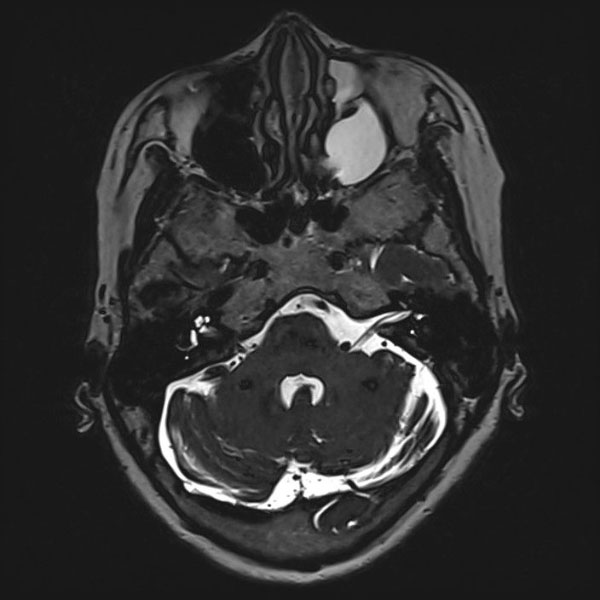

症例 '25年10月

No.

558

当院外来

'25年10月

60代

左顔面痙攣

(痙攣をとること)

手術前

減圧前

減圧後

術後血管撮影